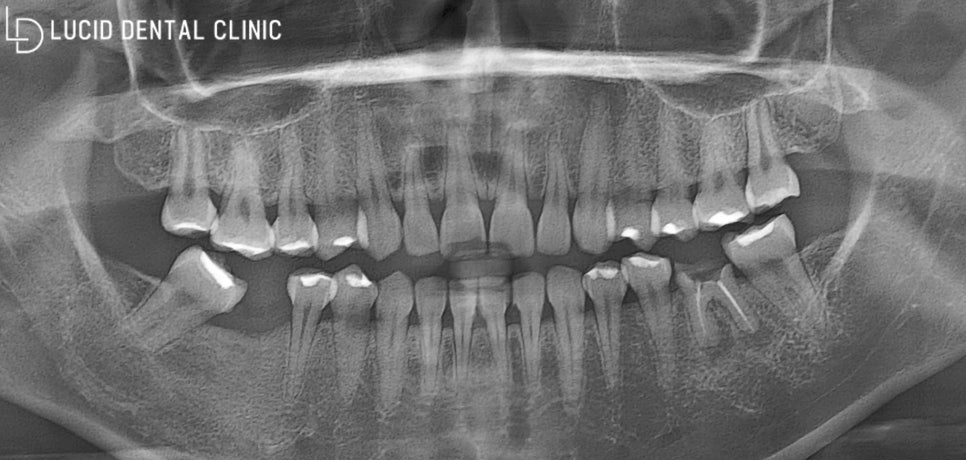

먼저 디지털 엑스레이 사진을 통해

환자의 구강 환경을 면밀히 살펴봤습니다.

환자께서 주소로 말씀해 주신 부분을

중점으로 조금 더 자세히 관찰해 볼게요.

먼저, 사진을 기준으로

왼쪽부터 살펴보겠습니다.